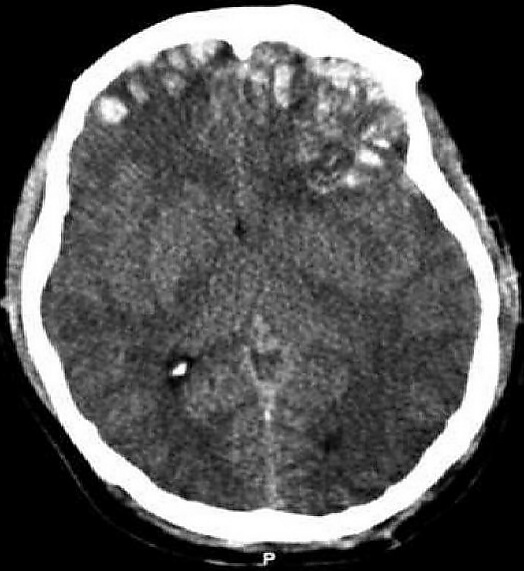

Ушиб головного мозга (лат. contusio cerebri) — черепно-мозговая травма, при которой происходит поражение непосредственно тканей головного мозга, всегда сопровождается наличием очага некроза нервной ткани. Наиболее часто очаги повреждения располагаются в области лобных, височных и затылочных долей. Повреждения, развившиеся при травме, могут быть как односторонние, так и двухсторонние[2].

Ушиб мозга средней степени тяжести характеризуется более продолжительной потерей сознания после травмы, нежели при легкой форме (от нескольких десятков минут до нескольких часов). После ушиба больные жалуются на сильную головную боль, наблюдается многократная рвота. Могут возникнуть нарушения психики. Встречается брадикардия или тахикардия, повышение АД, тахипноэ. Часто выражены менингеальные симптомы. Возможны переломы костей свода черепа и субарахноидальное кровоизлияние. Спинномозговая жидкость с выраженной примесью крови[2][4].

Ушиб мозга тяжелой степени характеризуется длительной потерей сознания после травмы (от нескольких часов до нескольких недель). Обычно выражено двигательное возбуждение. Наблюдается доминирование стволовых неврологических симптомов (множественный нистагм, нарушения глотания, двухсторонний мидриаз или миоз, горметония и др.). Могут выявляться парезы конечностей. Часто выражены менингеальные симптомы. Возможны переломы костей свода черепа и массивное субарахноидальное кровоизлияние. Тяжёлые ушибы мозга часто приводят к летальному исходу[2][4].